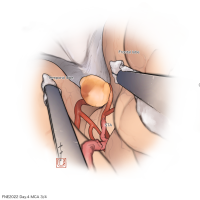

FEN2022シリーズ